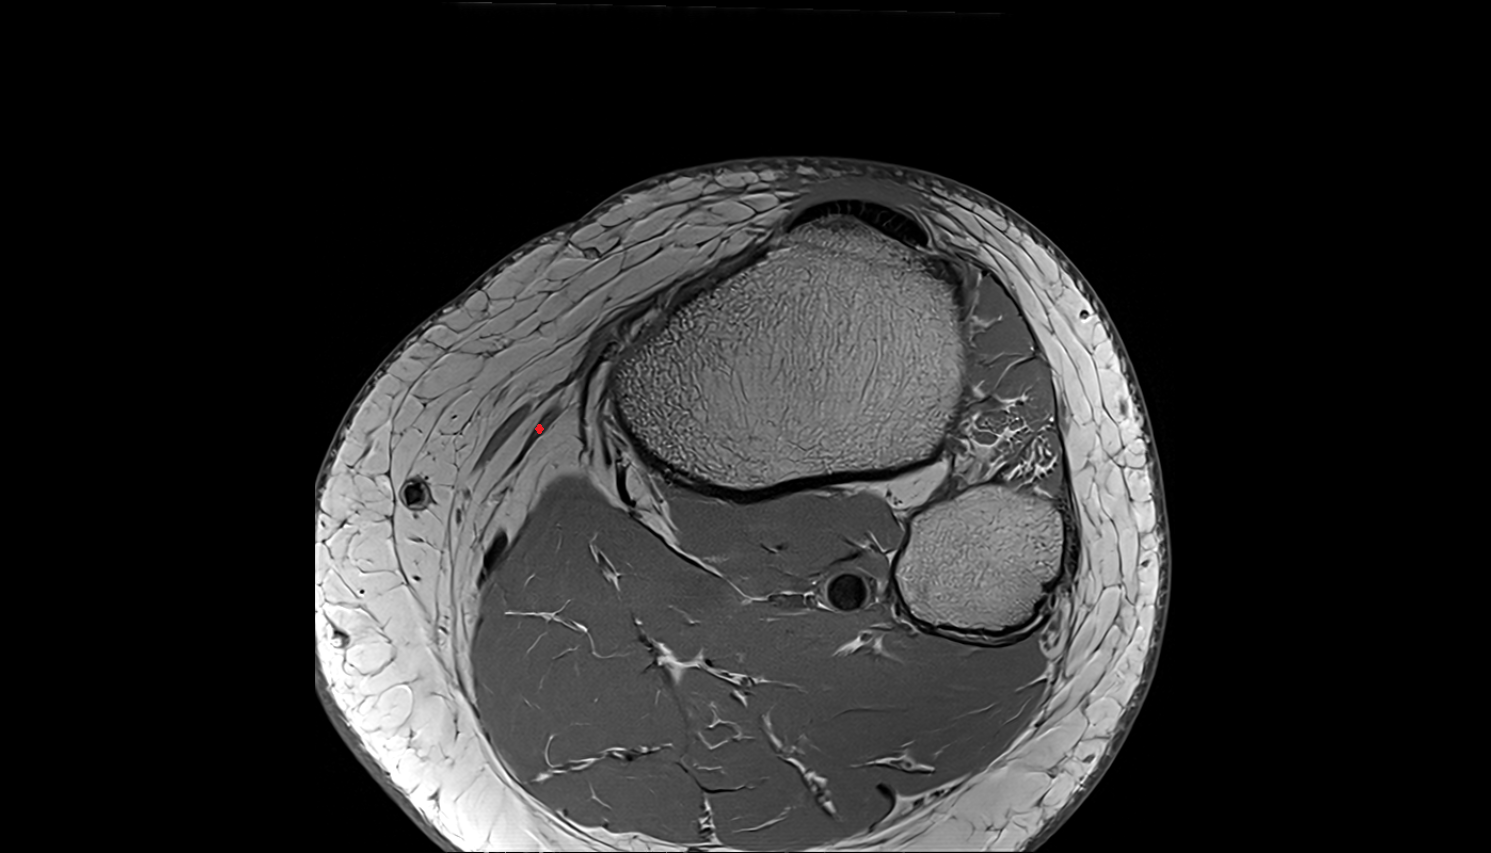

- Knee Joint